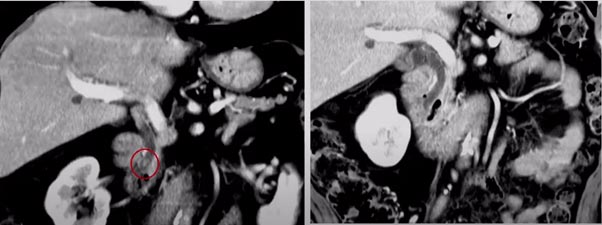

- Blockage classification – accurately imaging the cause of the blockage is key in treating it. Several imaging modalities are used for ERCP procedures, among them are computerized tomography (CT), X-ray and magnetic resonance cholangiopancreatography (MRCP). Deep learning and machine learning methods can be trained to accurately classify the blockage using features regarding geometry and texture as either cholelithiasis or strictures (either benign or malignant).